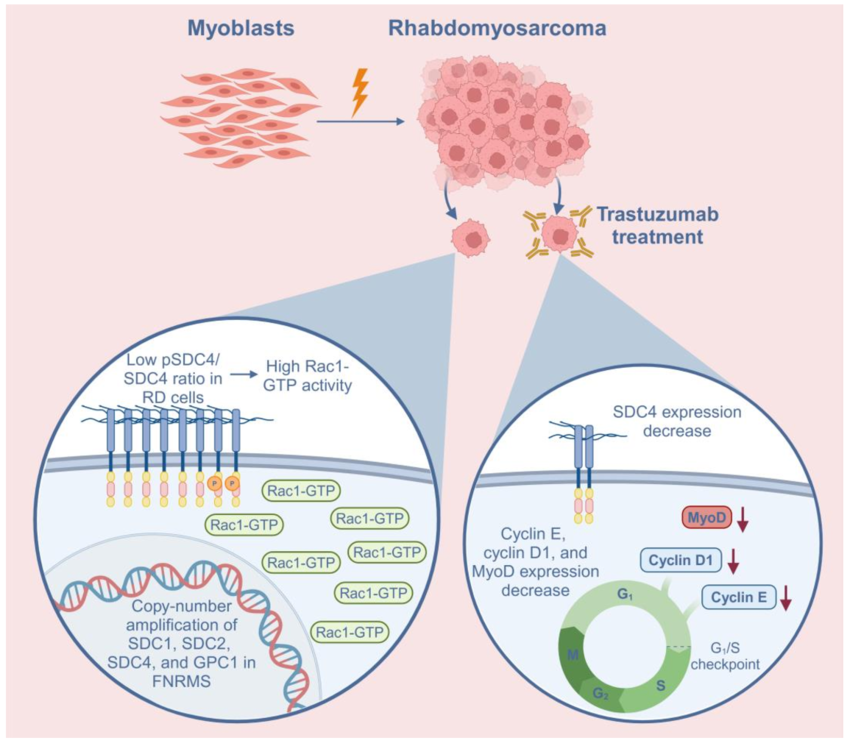

Rhabdomyosarcoma, the most common soft tissue sarcoma in children, arises from skeletal muscle cells that fail to differentiate terminally. As a result, instead of forming mature muscle tissue, the tumor cells grow uncontrollably. Studying how muscle cell differentiation is disrupted in RMS could help identify potential treatments that target these molecular mechanisms, either promoting normal muscle formation or preventing tumor cells from becoming more undifferentiated and cancerous.

Two subgroups of rhabdomyosarcoma, fusion-positive and fusion-negative rhabdomyosarcoma (FPRMS and FNRMS, respectively), are characterized by the presence or absence of the PAX3/7-FOXO1 fusion gene. Rhabdomyosarcomas frequently exhibit increased expression of human epidermal growth factor receptor-2 (HER2). Since HER2 is expressed in about half of rhabdomyosarcomas, the trastuzumab-mediated changes observed here may have therapeutic implications.